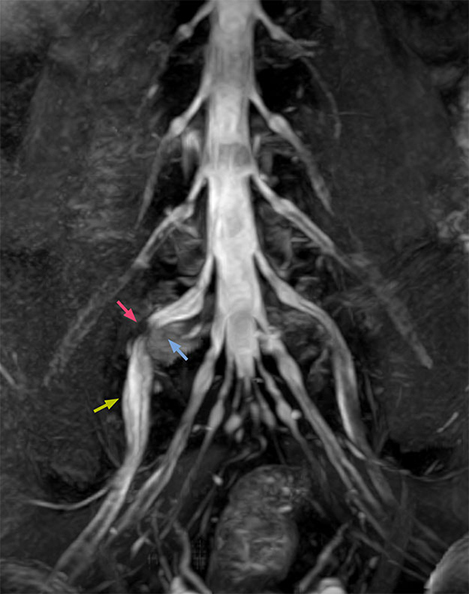

“NerveVIEW can clearly show nerve courses and presence of nerve compression. However, when multiple abnormalities are seen, it can still be hard to determine which nerve is causing the symptoms,” says Dr. Yabuki. “In our experience so far, we see abnormal findings on NerveVIEW in about 70% of elderly patients. As the pain is usually caused by only one nerve, we thus need to find the exact corresponding nerve.” “With a nerve root block, the patient's pain is improved by infiltration of local anesthesia directly around the nerve root considered to be responsible. Knowing such nerve root block findings prior to image interpretation, helps to easily recognize abnormal findings on NerveVIEW as well. In other words, without a priori knowledge, based on symptoms and/or nerve root block findings, we must be aware of the possibility of overdiagnosis.”

“Although symptoms of typical disc herniation and atypical hernia are very similar, the actual site of herniation is different. It is therefore important to characterize the nerve’s condition both inside and outside of the intervertebral foramina. “Conversely, if we see no abnormality in NerveVIEW, we can assume at least that there is no severe condition that requires surgery. Like this, it can help us avoid unnecessary surgery. NerveVIEW can have a tremendous impact in this way.”

“NerveVIEW is really useful for those cases where a nerve disorder is strongly suspected based on the clinical examination but our regular MRI images do not show any findings. These atypical herniations and spinal canal stenosis, occurring in 5% to 15% of the total lumbar herniation/stenosis cases are our main target when using NerveVIEW,” says Dr. Yabuki.

“Recently, the two surgical methods extreme and oblique lateral interbody fusion (XLIF and OLIF) have become mainstream for minimally invasive treatment of lumbar spinal canal stenosis and intervertebral foramen stenosis. With these surgical techniques, the spine is approached from the flank, and prior knowledge of the exact anatomy of the lumbosacral plexus would be extremely helpful. To that end, high slice resolution (less than 1 mm acquisition) that enables sharper sagittal MPR images will be needed.”